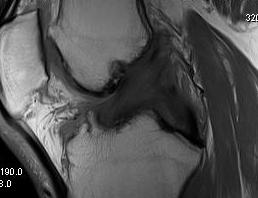

Coronal MRI of left knee demonstrating proximal MCL tear, with sagittal demonstrating complete disruption of ACL / PCL